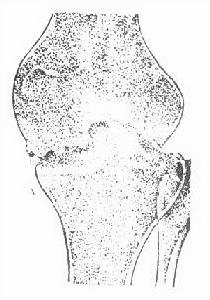

1.骨結核 按骨的緻密程度可分為松質骨(或稱海綿骨)和密質骨(或稱皮質骨) 松質骨結核可分為中心型和邊緣型兩種。中心型結核以浸潤及壞死為主,壞死骨組織游離後形成死骨 死骨吸收後遺留骨空洞;邊緣型結核不易形成大塊死骨,較小死骨也常被吸收或排出,形成局限性骨缺損。密質骨結核多自髓腔開始,以局限性骨性破壞為主,一般不形成死骨。所生膿液可沿Volkmann管匯集到骨膜下,將骨膜掀起,並刺激骨膜,形成新骨。反覆多次,骨膜新骨呈現蔥皮樣外觀。管狀骨幹骺端結核是有松質骨和密質骨這兩種結核的特點。

單純骨結核可見局部有溶骨性破壞,磨砂玻璃樣改變或死骨形成。